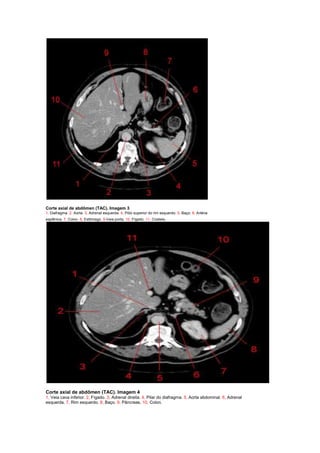

Corte axial de abdômen (TAC). Imagem 1.

1, Pulmão direito. 2, veia hepática direita. 3, Fígado. 4, veia hepática esquerda. 5, Estômago. 6, flexura esquerda do

colo (flexura esplênica). 7, Baço. 8, Pulmão esquerdo. 9, Aorta.

1, Pulmão direito. 2, Aorta. 3, Pulmão esquerdo. 4, Adrenal esquerda. 5, Baço. 6, Artéria esplênica. 7, Colon. 8, Veia

porta. 9,Veia hepática. 10, Fígado.

Corte axial de abdômen (TAC). Imagem 3

1, Diafragma. 2, Aorta. 3, Adrenal esquerda. 4, Pólo superior do rim esquerdo. 5, Baço. 6, Artéria

esplênica. 7, Colon. 8, Estômago. 9,Veia porta. 10, Fígado. 11, Costela.

Corte axial deabdômen (TAC). Imagem 1. 1, Pulmão direito. 2, veia hepática direita. 3, Fígado. 4, veia hepática esquerda. 5, Estômago. 6, flexura esquerda do colo (flexura esplênica). 7, Baço. 8, Pulmão esquerdo. 9, Aorta. 1, Pulmão direito. 2, Aorta. 3, Pulmão esquerdo. 4, Adrenal esquerda. 5, Baço. 6, Artéria esplênica. 7, Colon. 8, Veia porta. 9,Veia hepática. 10, Fígado.

Corte axial deabdômen (TAC). Imagem 3 1, Diafragma. 2, Aorta. 3, Adrenal esquerda. 4, Pólo superior do rim esquerdo. 5, Baço. 6, Artéria esplênica. 7, Colon. 8, Estômago. 9,Veia porta. 10, Fígado. 11, Costela. Corte axial de abdômen (TAC). Imagem 4 1, Veia cava inferior. 2, Fígado. 3, Adrenal direita. 4, Pilar do diafragma. 5, Aorta abdominal. 6, Adrenal esquerda. 7, Rim esquerdo. 8, Baço. 9, Pâncreas. 10, Colon.